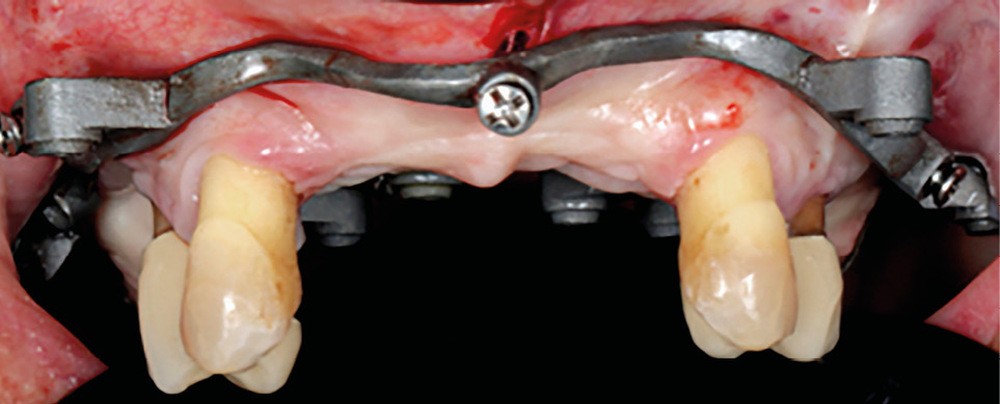

Une patiente de 62 ans, non fumeuse Asa1, porteuse d’une prothèse amovible partielle (PAP) mandibulaire et maxillaire, souhaite bénéficier d’une solution fixée. Il persiste au maxillaire 13, 23, 14 et 24, associées à une forte résorption type FP3 [1, 2] (fig. 1).

La première étape du protocole des guides à étages (Your3DGuide) est la connexion du guide de positionnement à appui dentaire à la base crâniale métallique hors de la bouche (fig. 4). Cette dernière sera fixée à l’aide de vis transmuqueuses vestibulaires et palatines (fig. 5). Nous avons choisi ce système car la base titane est frittée par laser, ce qui lui conférerait une précision d’adaptation et une rigidité supérieure à une base résine tout en conservant une faible épaisseur. Sur cette base vont se visser les autres étages assurant une stabilisation et évitant un éventuel mouvement lors du forage (et lors de la solidarisation du provisoire).